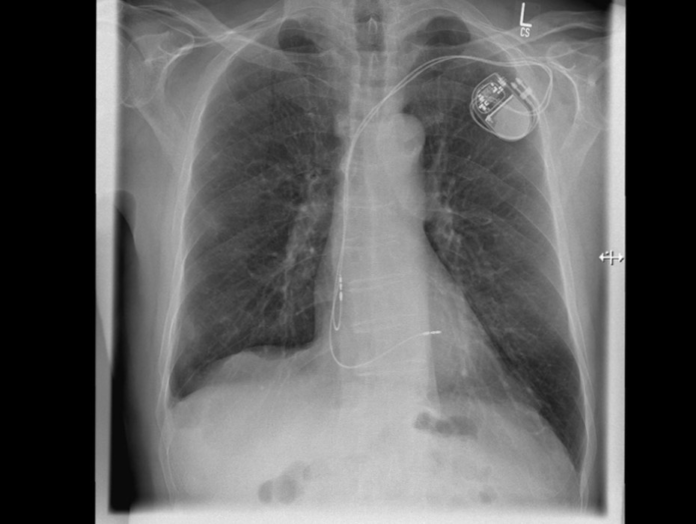

Für diese Patienten kommt eine minimalinvasive Herzklappenintervention infrage. Dabei ist keine Herzoperation mit Verwendung einer Herz-Lungen-Maschine notwendig. Stattdessen findet der Eingriff mittels Katheter über die Leistenvene statt. Über den Katheter, einen dünnen Kunststoffschlauch, wird ein Clip zum Herzen geführt. Dabei können die Segel der Mitralklappe mit einem MitraClip bzw. der Trikuspidalklappe mit einem TriClip gefasst und geclippt werden. Dadurch halten die Segel wieder zusammen und die Undichtigkeit der Klappen wird deutlich reduziert. Während der Untersuchung wird unter Narkose eine kontinuierliche Überwachung mit Ultraschall, einer transösophagealen Echokardiographie, durchgeführt. Dadurch können die Clips jederzeit geortet und optimal platziert werden.

Das Eingriffsrisiko bei der Implantation eines MitraClip oder TriClip ist deutlich geringer als bei einer Operation. Ob das Verfahren individuell infrage kommt, muss von einem Heart Team, bestehend aus Fachärzten der Kardiologie, Herzchirurgie und Anästhesie, beurteilt werden. „In der Kardiologie des Diakonie Klinikums Jung-Stilling in Siegen wird diese moderne Methode zur Herzklappenreparatur regelmäßig und mit Erfolg angewandt. Dadurch sind wir nicht nur in der Region Siegen, sondern auch rund um Köln/Bonn, Bochum, Dortmund und in Hessen bereits als kompetenter Ansprechpartner bekannt und eine überregionale Anlaufstelle für viele Herzpatienten“, betont Prof. Dr. Dursun Gündüz, Chefarzt der Kardiologie am Diakonie Klinikum Jung-Stilling in Siegen.